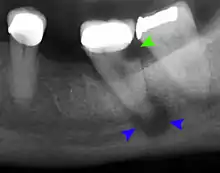

Clinical & xray correlation of pericoronitis

clinical shot of pericoronitis

An operculum (green arrow) over a partially erupted lower left third molar tooth. There is minimal inflammation and recurrent swelling.

xray of pericoronitis

A radiograph of the above tooth showing chronic pericoronitis, operculum (blue arrow) and bone destruction (red arrow) from chronic inflammation. Tooth is slightly disto-angular.

Pericoronitis is inflammation of the soft tissues surrounding the crown of a partially erupted tooth.[25] The lower wisdom tooth is the last tooth to erupt into the mouth, and is, therefore, more frequently impacted, or stuck, against the other teeth. This leaves the tooth partially erupted into the mouth, and there frequently is a flap of gum (an operculum), overlying the tooth. Bacteria and food debris accumulate beneath the operculum, which is an area that is difficult to keep clean because it is hidden and far back in the mouth. The opposing upper wisdom tooth also tends to have sharp cusps and over-erupt because it has no opposing tooth to bite into, and instead traumatizes the operculum further. Periodontitis and dental caries may develop on either the third or second molars, and chronic inflammation develops in the soft tissues. Chronic pericoronitis may not cause any pain, but an acute pericoronitis episode is often associated with pericoronal abscess formation. Typical signs and symptoms of a pericoronal abscess include severe, throbbing pain, which may radiate to adjacent areas in the head and neck,[21][26]:122 redness, swelling and tenderness of the gum over the tooth.[27]:220–222 There may be trismus (difficulty opening the mouth),[27]:220–222 facial swelling, and rubor (flushing) of the cheek that overlies the angle of the jaw.[21][26]:122 Persons typically develop pericoronitis in their late teens and early 20s,[28]:6 as this is the age that the wisdom teeth are erupting. Treatment for acute conditions includes cleaning the area under the operculum with an antiseptic solution, painkillers, and antibiotics if indicated. After the acute episode has been controlled, the definitive treatment is usually by tooth extraction or, less commonly, the soft tissue is removed (operculectomy). If the tooth is kept, good oral hygiene is required to keep the area free of debris to prevent recurrence of the infection.[21]:440–441